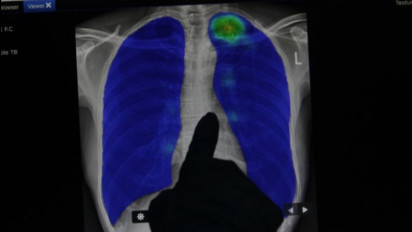

Arsip Foto - Petugas medis memperlihatkan hasil rontgen paru-paru dalam kegiatan pemeriksaan di SDN Duren Tiga 01, Jakarta, Selasa (19/12/2023).

• (ANTARA FOTO/Rina Nur Anggraini/Ak/rwa)